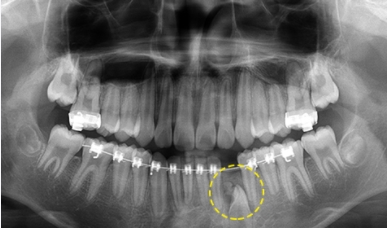

3. 치아종

치아종은 치아가 작은 덩어리로 여러 개 뭉쳐잇는 것을 말하며 복합 치아종과 복잡 치아종으로 나눠집니다.

치아종 제거 후 치아교정을 통해 맹출되지 못한 치아를 맹출 시킵니다.